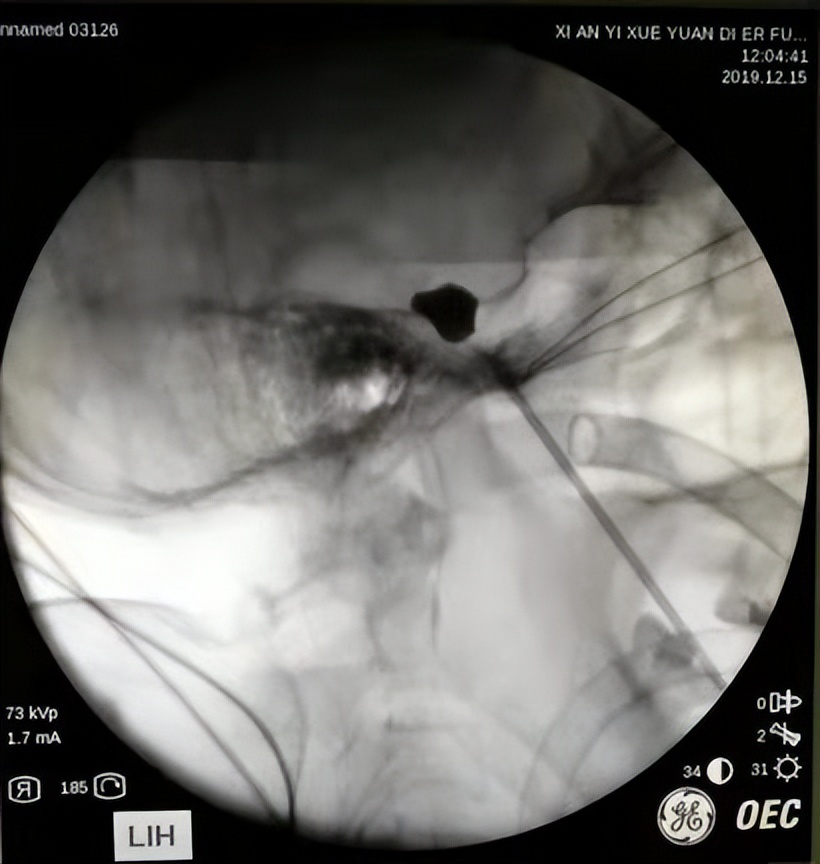

3、球囊压迫术。这种手术也是我们神经外科常用的手术方法之一,它属于神经损毁术,在x线或CT引导下在三叉神经半月节置入球囊让病变神经根损毁,阻断痛觉传导。对于高龄、不耐受开颅手术、身体素质不好、有多种基础病等患者来说,不能进行显微血管减压术,退而求其次,这种方法也算是较好的选择。